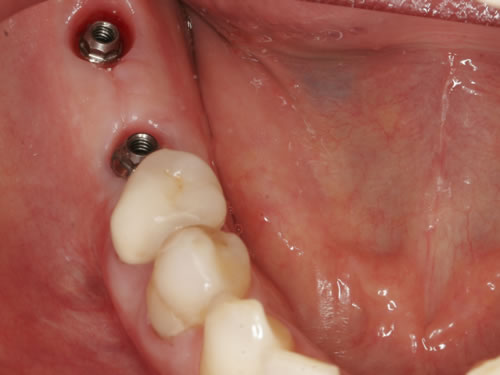

Abb. 8.1: Freigelegte Implantate in einer Schaltlücke mit Einheilkappen versorgt.

Nach der Einheilung müssen die Implantate, die unter der Schleimhaut liegen, eröffnet werden. Dies ist aber meistens nur eine sehr kleine Maßnahme, die wieder in örtlicher Betäubung durchgeführt wird (Abb. 8.1).

Bei oberen Frontzähnen wird mit bestimmten Freilegungstechniken das Zahnfleisch zur Lippe häufig noch etwas korrigiert. Die Freilegung bietet sich für die Maßnahme an, da zwangsläufig Zahnfleisch und Bindegewebe bei der Eröffnung anfallen (Abb. 8.2 bis 8.4). In die Implantate werden Einheilkappen oder Gingivaformer eingesetzt, damit es in der Abheilungsphase nicht zu einem erneuten Zuwachsen der Schleimhaut kommt.